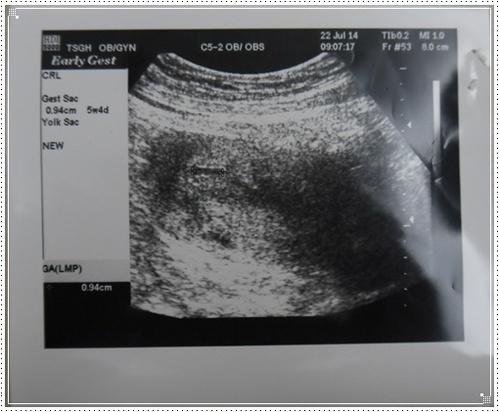

7/21 驗孕

7周時終於看到心跳了,醫生好高興,覺得這次應該沒問題

總之就是,這次拉拉已經有5.68CM囉!

醫生說這個大小已經算是滿12周,度過前3個月的流產危險期囉!